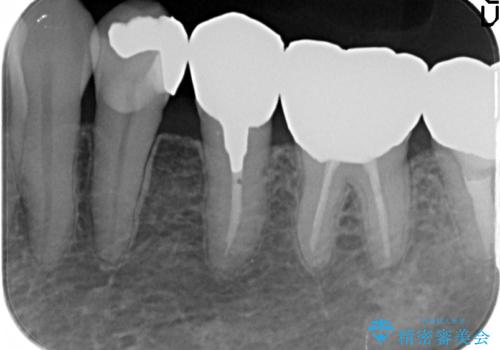

- 左下5番目の歯を根管治療からやり直したいといらっしゃった方の症例です。

再根管治療終了後、オールセラミッククラウンによる補綴を行いました。